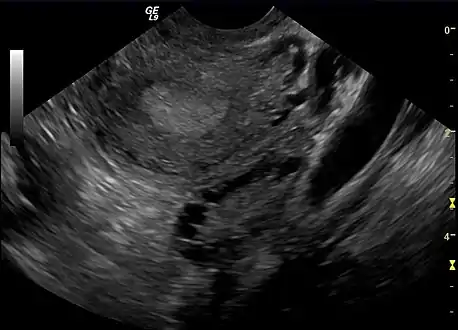

The syndrome acquired its most widely used name due to the common sign on ultrasound examination of multiple (poly) ovarian cysts. These "cysts" are in fact immature ovarian follicles. The follicles have developed from primordial follicles, but this development has stopped ("arrested") at an early stage, due to the disturbed ovarian function. The follicles may be oriented along the ovarian periphery, appearing as a 'string of pearls' on ultrasound examination.[86]

Polycystic ovary as seen on sonography

- Gynecologic ultrasonography, specifically looking for small ovarian follicles. These are believed to be the result of disturbed ovarian function with failed ovulation, reflected by the infrequent or absent menstruation that is typical of the condition. In a normal menstrual cycle, one egg is released from a dominant follicle – in essence, a cyst that bursts to release the egg. After ovulation, the follicle remnant is transformed into a progesterone-producing corpus luteum, which shrinks and disappears after approximately 12–14 days. In PCOS, there is a so-called "follicular arrest"; i.e., several follicles develop to a size of 5–7 mm, but not further. No single follicle reaches the preovulatory size (16 mm or more). According to the Rotterdam criteria, which are widely used for diagnosis of PCOS,[10] 12 or more small follicles should be seen in a suspect ovary on ultrasound examination.[21] More recent research suggests that there should be at least 25 follicles in an ovary to designate it as having polycystic ovarian morphology (PCOM) in women aged 18–35 years.[95] The follicles may be oriented in the periphery, giving the appearance of a 'string of pearls'.[96] If a high-resolution transvaginal ultrasonography machine is not available, an ovarian volume of at least 10 ml is regarded as an acceptable definition of having polycystic ovarian morphology. rather than follicle count.[95]

Ultrasound findings in PCOS include enlarged ovaries with peripheral follicles in a "string of pearls" configuration.